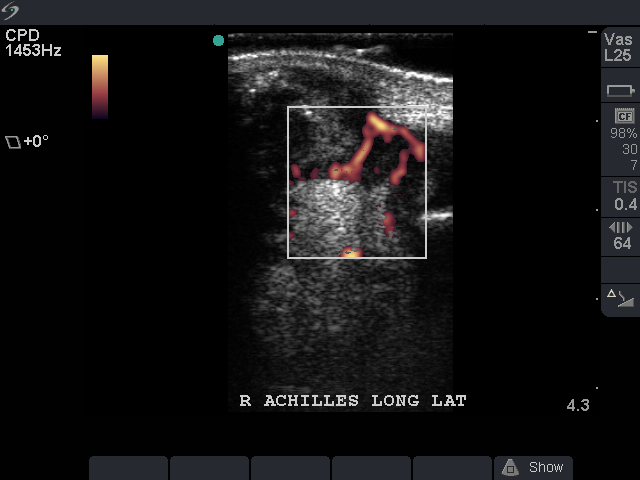

Achilles Tendon: Power Doppler correlation depicting acute nature of swelling.

Achilles Tendon: Intrasubstance tearing acute power doppler activity